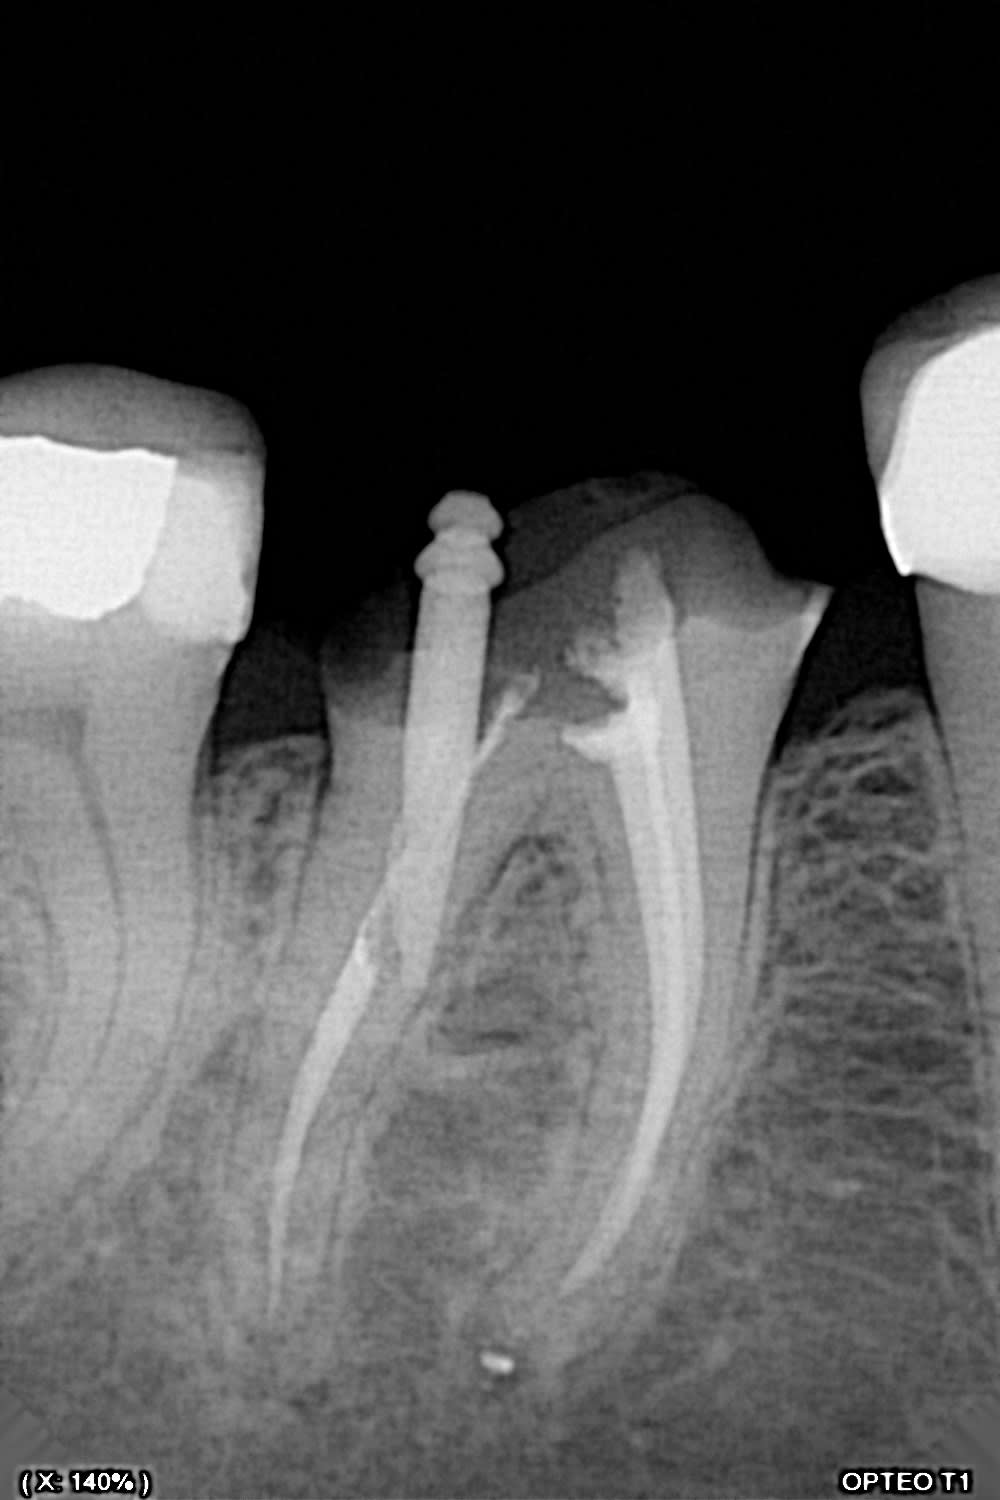

Moi j'ai fait ça la semaine dernière (et je ne suis vraiment pas fier).

Pas de douleurs pas de saignement au forage. La patiente me dit: ah, j'ai un peu mal quand j'appuis dessus...

Que feriez vous?

Finalement, séance suivante: mise en évidence d'un saignement dans le logement du tenon.

Obturation à la biodentine que j'ai fait "descendre dans le logement du tenon " avec un insert fin sans eau.

Disparition des symptômes la semaine suivante.

Contrôle à 6 mois, dent asymptomatique, radio encourageante.

voila